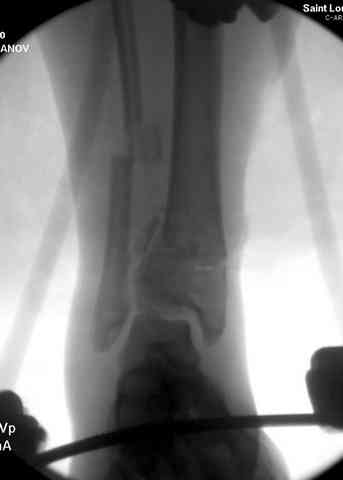

Снова приветствую вас, коллеги. К моменту вступления в обсуждение аксакалов, операция была, увы, выполнена(31.10.07.) Начали с доступа к наружной лодыжке, произвели ее фиксацию спицами, развернули кусок заднего края, наложили дистрактор, затем произвели дистракцию, фиксацию спицами дистального эпиметафиза б/бк,Рентгено-контроль. синтез наружной лодыжки 1/3пластиной. из двух коротких разрезов сформирован канал под медиальную тибиальную пластину LCP. Края ран ушиты без натяжения. Прочувствовать жесткость фиксации винтами с угловой стабильностью не удалось, поэтому дистрактор оставлен на энное время.

На представленных R-снимках не окончательный вид после остеосинтеза. Дистальная опора давила на стопу, пришлось ее сместить проксимально, в рез-те чего, она закрыла щель сустава, последние снимки не информативны.

Причина нарастающего отёка скорее всего нестабильная фиксация,либо начинающая инфекция.

У меня вопрос. Почему проксимальный фрагмент с медиально стороны фиксированк плате всего одним болтом.

Дистальные винты как-то чуть не все идут не в дистальные отломки, а в зону перелома. И действительно, присоединяюсь к вопросу Якова - в диафизе так и оставили 1 винт?